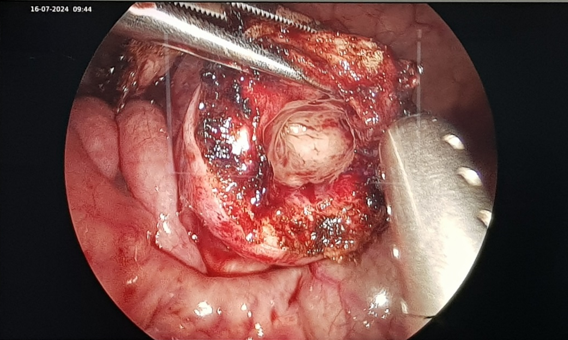

được chẩn đoán “Nang ruột đôi”, trẻ có chỉ định phẫu thuật cắt nang bằng kỹ

thuật nội soi. Sau 1 giờ phẫu thuật, kíp phẫu thuật gồm: BS CKI Nguyễn Mạnh

Toàn,BS CK I Nguyễn Quốc Khánh, BS Gây mê CK I Phan Thị Hoài Nam đã phẫu thuật

cắt chỏm nang ruột đôi thành công.

Ảnh cắt nang ruột đôi trong mổ nội soi